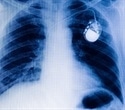

A pacemaker is a small battery-operated electronic device placed in your body, usually by surgery, to help stabilize and regulate abnormal heart rhythms to a more regular pattern. A temporary pacemaker helps a recovering heart to manage a slow heartbeat (bradycardia) after a heart attack. In these cases, the pacemaker may be attached to the clothes rather than implanted under the skin. Permanent pacemakers are implanted in patients with chronic heart failure or a slow or irregular heartbeat.

The pacemaker is implanted underneath the chest skin just below the collar bone and connected to the heart with tiny wires. The whole procedure takes around an hour to complete.

The electrodes, one to three in number, are placed in one or more chambers of the heart to deliver the electrical pulses to adjust the heart rate. Modern leadless pacemakers, however, are implanted directly into the heart muscle. Chest radiography helps doctors identify the pacemaker and the lead type, the lead course within the heart, and the type of lead fixation to the myocardium. The pacemaker leads have a lifespan of approximately eight to 10 years.